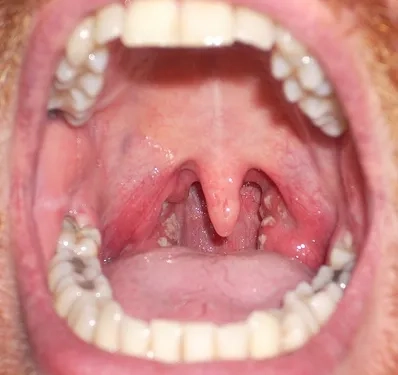

Key Symptoms of Chlamydia to Watch For

• Common chlamydia symptoms in women include abnormal vaginal discharge, a burning sensation when urinating, and pain during intercourse.

• For chlamydia symptoms in men, look for penile discharge, testicular pain, and a burning sensation during urination.